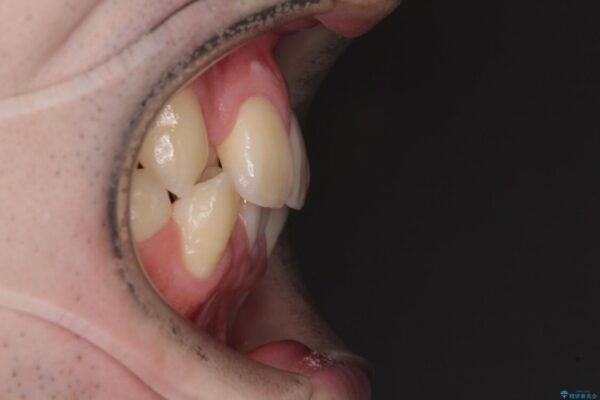

八重歯や奥歯の噛みにくさを気にして来院された患者様です。

前歯のクロスバイトや八重歯の他に、左右最後臼歯のシザーズバイト(鋏状咬合)が認められました。

治療前

• 全顎的なクロスバイト 補助装置を用いてワイヤー矯正 治療前画像